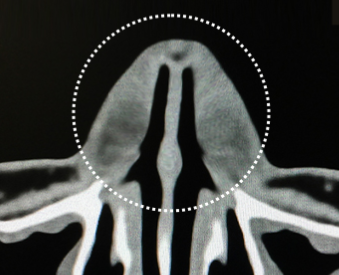

수술 전 정밀 진단

3D-CT와 비내시경

3D-CT |

BEFORE | AFTER | ||

최첨단 3D-CT를 통해 육안으로 식별이 불가능한 코의 골격과 구조 등

기능적인 문제를 정확하게 진단합니다.

비중격만곡증, 비염, 비밸브협착의 유무 등을 확인하여

기능적인 문제점을 보다 정확하게 개선할 수 있습니다.